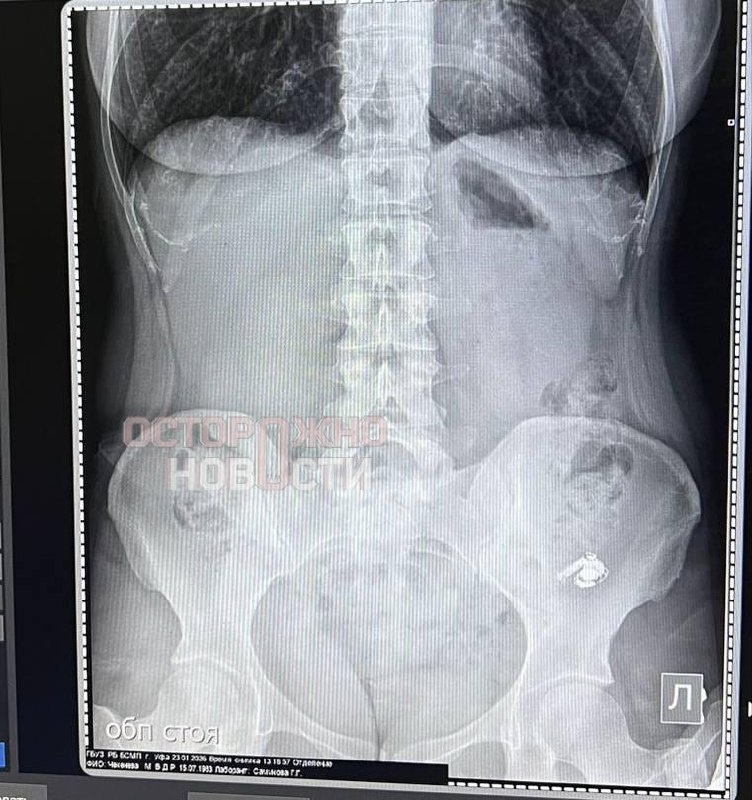

Привет, друзья! Недавно в Уфе произошёл курьёзный случай: местная жительница проглотила AirPods, перепутав его с таблетками. Это напоминает о том, как важно быть внимательными и осторожными, особенно когда речь идёт о приёме лекарств.

Случай с Марией, которая проглотила наушник, может показаться забавным, но он подчёркивает серьёзность проблемы неправильного приёма медикаментов. Согласно статистике, ошибки при приёме лекарств могут иметь серьёзные последствия для здоровья. По данным ВОЗ, ежегодно в мире из-за таких ошибок страдают миллионы людей. Важно помнить, что даже небольшая невнимательность может привести к серьёзным последствиям.